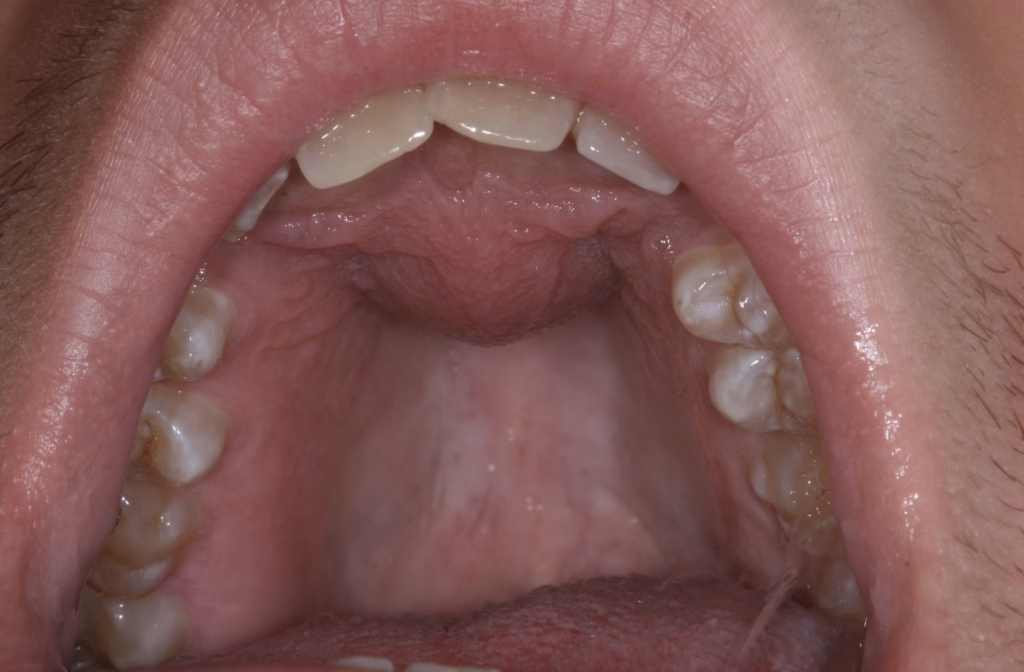

1. Nasopalatine Duct Cyst

The most common one dentists see.

This cyst forms behind the upper front teeth, in a natural canal that exists in everyone.

- A bump in the middle of the palate (roof of the mouth)